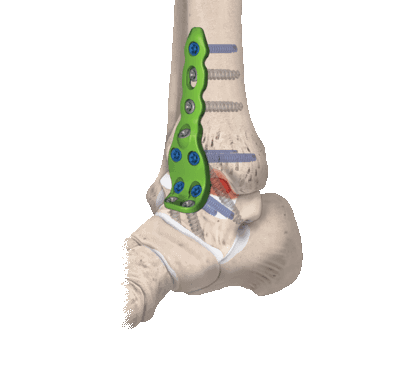

в) Техника операции ревизионной артропластики. Ревизионная артропластика (рис. 7) показана при соблюдении следующих условий:

• Достаточный для адекватной фиксации импланта запас костной ткани таранной кости (см. рис. 1)

• Состояние костной ткани, способное обеспечить адекватную фиксацию и остеоинтеграцию импланта (см. рис. 2)

• Возможность коррекции сопутствующих проблем (например, восстановление стабильности голеностопного сустава, формы заднего отдела стопы)